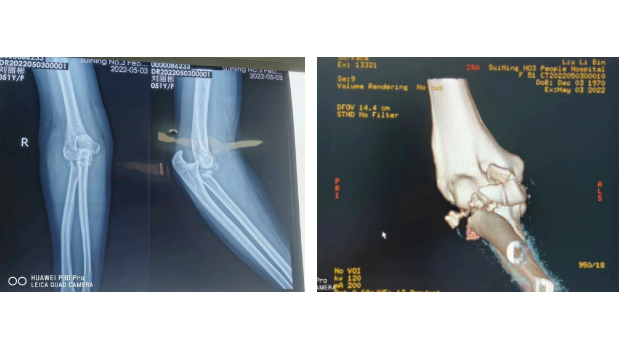

三管齐下!让“肘关节恐怖三联征”不再恐怖!

我院骨伤科为一位肘关节复杂骨折伴脱位患者成功实施了标准化手术,重建了一个“稳定、有力、活动良好”的肘关节。目前,该患者肘关节功能恢复良好,已康复出院。家住城南的...

“恐怖三联征”不再恐怖,我院骨伤科又顺利完成一例复杂肘关节手术

本月中旬,我院骨伤科为一位肘关节复杂骨折伴脱位患者成功实施了标准化手术,重建了一个“稳定、有力、活动良好”的肘关节。目前,该患者肘关节功能恢复良好,已康复出院。...